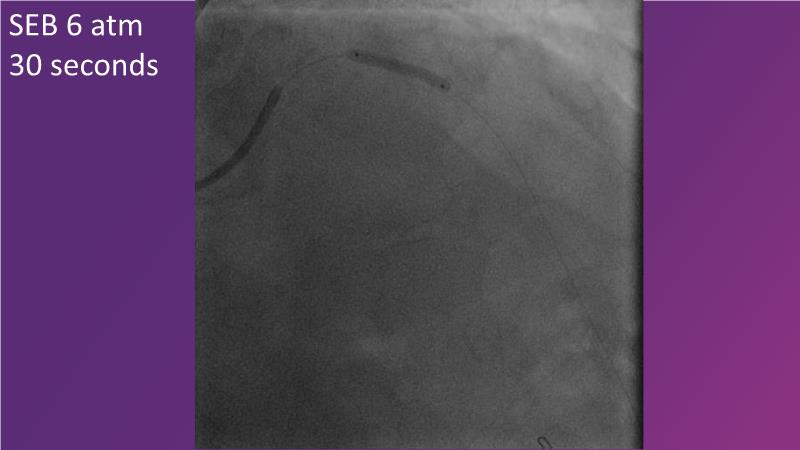

- To discuss how sustained limus release technology can broaden DEB indications and reduce metal

- To learn about the importance of vessel preparation and which tool to use when